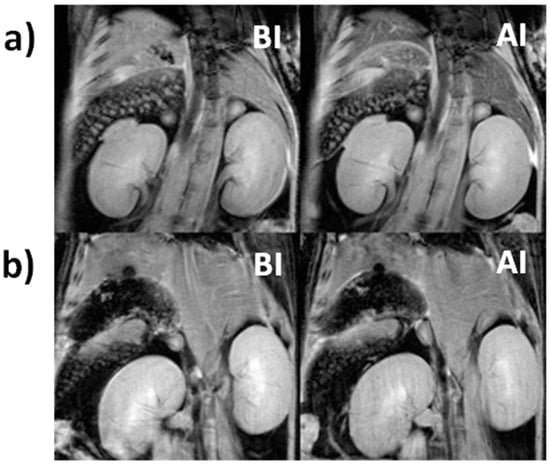

3.3. In Vivo MRI Results